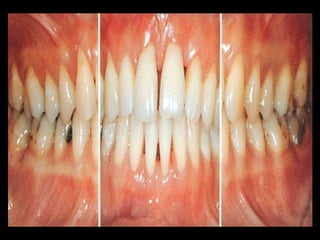

DESTRUCTIVE STAGE:

severe acutely inflammed tissue

Ulcerative

fiery red

bleeding may occur spontaneously or on

stimulation pressure

Suppuration maybe an important feature

Attachment & bone are actively lost

OTHER CASES:

Gingival tissues may appear pink

Free of inflammation

Absence of some degree of stippling

Deep pockets demonstrated by probing

DESTRUCTIVE STAGE: severe acutelyinflammed tissue Ulcerative fiery red bleeding may occur spontaneously or on stimulation pressure Suppuration maybe an important feature Attachment & bone are actively lost

OTHER CASES: Gingival tissuesmay appear pink Free of inflammation Absence of some degree of stippling Deep pockets demonstrated by probing Systemic manifestations: Weight loss Mental depression Malaise